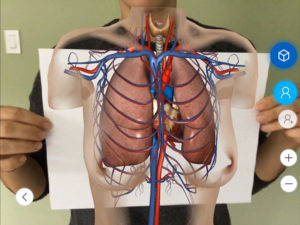

Complex medical subject matter is poorly illustrated and in standard teaching materials. Also, healthcare professionals and students often struggle with conventional imagery and two-dimensional diagrams when trying to understand complex scenarios.

AR applications are ideal ways to better illustrate complex concepts. Trainees no longer have to visualize the two dimensional subject matter in 3D, the subject matter in question is represented, as it is in practice, right in front of them. While it does not replace traditional simulation, trainees can now practice without the need for individual mannequins or subject matter experts using AR. This reduces the cost, but also the man hours needed to qualify trainees.

Unlike traditional classroom teaching aids, AR applications allow trainees to manipulate the subject matter as they needed to gain the proper insights. Through engaging and interactive materials the training is remembered longer, completed quicker, and results in better on the job decision making. For subjects such as Breech Births, Chest Emergencies, and Sepsis, quickly recognizing these conditions is important to proper treatment and patient health.

These application are used regularly across the NHS in both clinical and non-clinical teaching contexts, supporting faster learning with powerful visuals and anatomical models – a real boon for busy doctors, nurses, consultants, and their trainees.